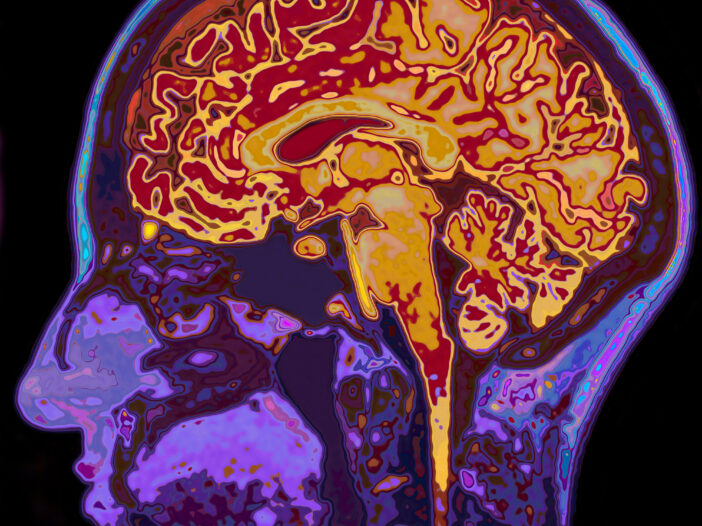

Neurology, simply put, is the branch of medicine that treats disorders of the nervous system. That encompasses the brain, brain stem, nerves and spinal cord. The largest part of the field is the central nervous system, where we find control of our most basic behaviors—movements, speech, understanding and balance.

Central Maine’s Department of Neurology treats adults for disorders such as stroke, epilepsy, neurodegenerative diseases such as Alzheimer’s, movement disorders such as Parkinson’s, dementia, cognitive disorders and more. If it’s a disorder of your brain or spinal cord, we treat it in Neurology.

Symptoms of neurological disorders aren’t easy to navigate, but we’re here to help. Our board-certified neuroscience team is trained to diagnose and treat the full range of diseases linked to the brain, spine, muscles and nerves.